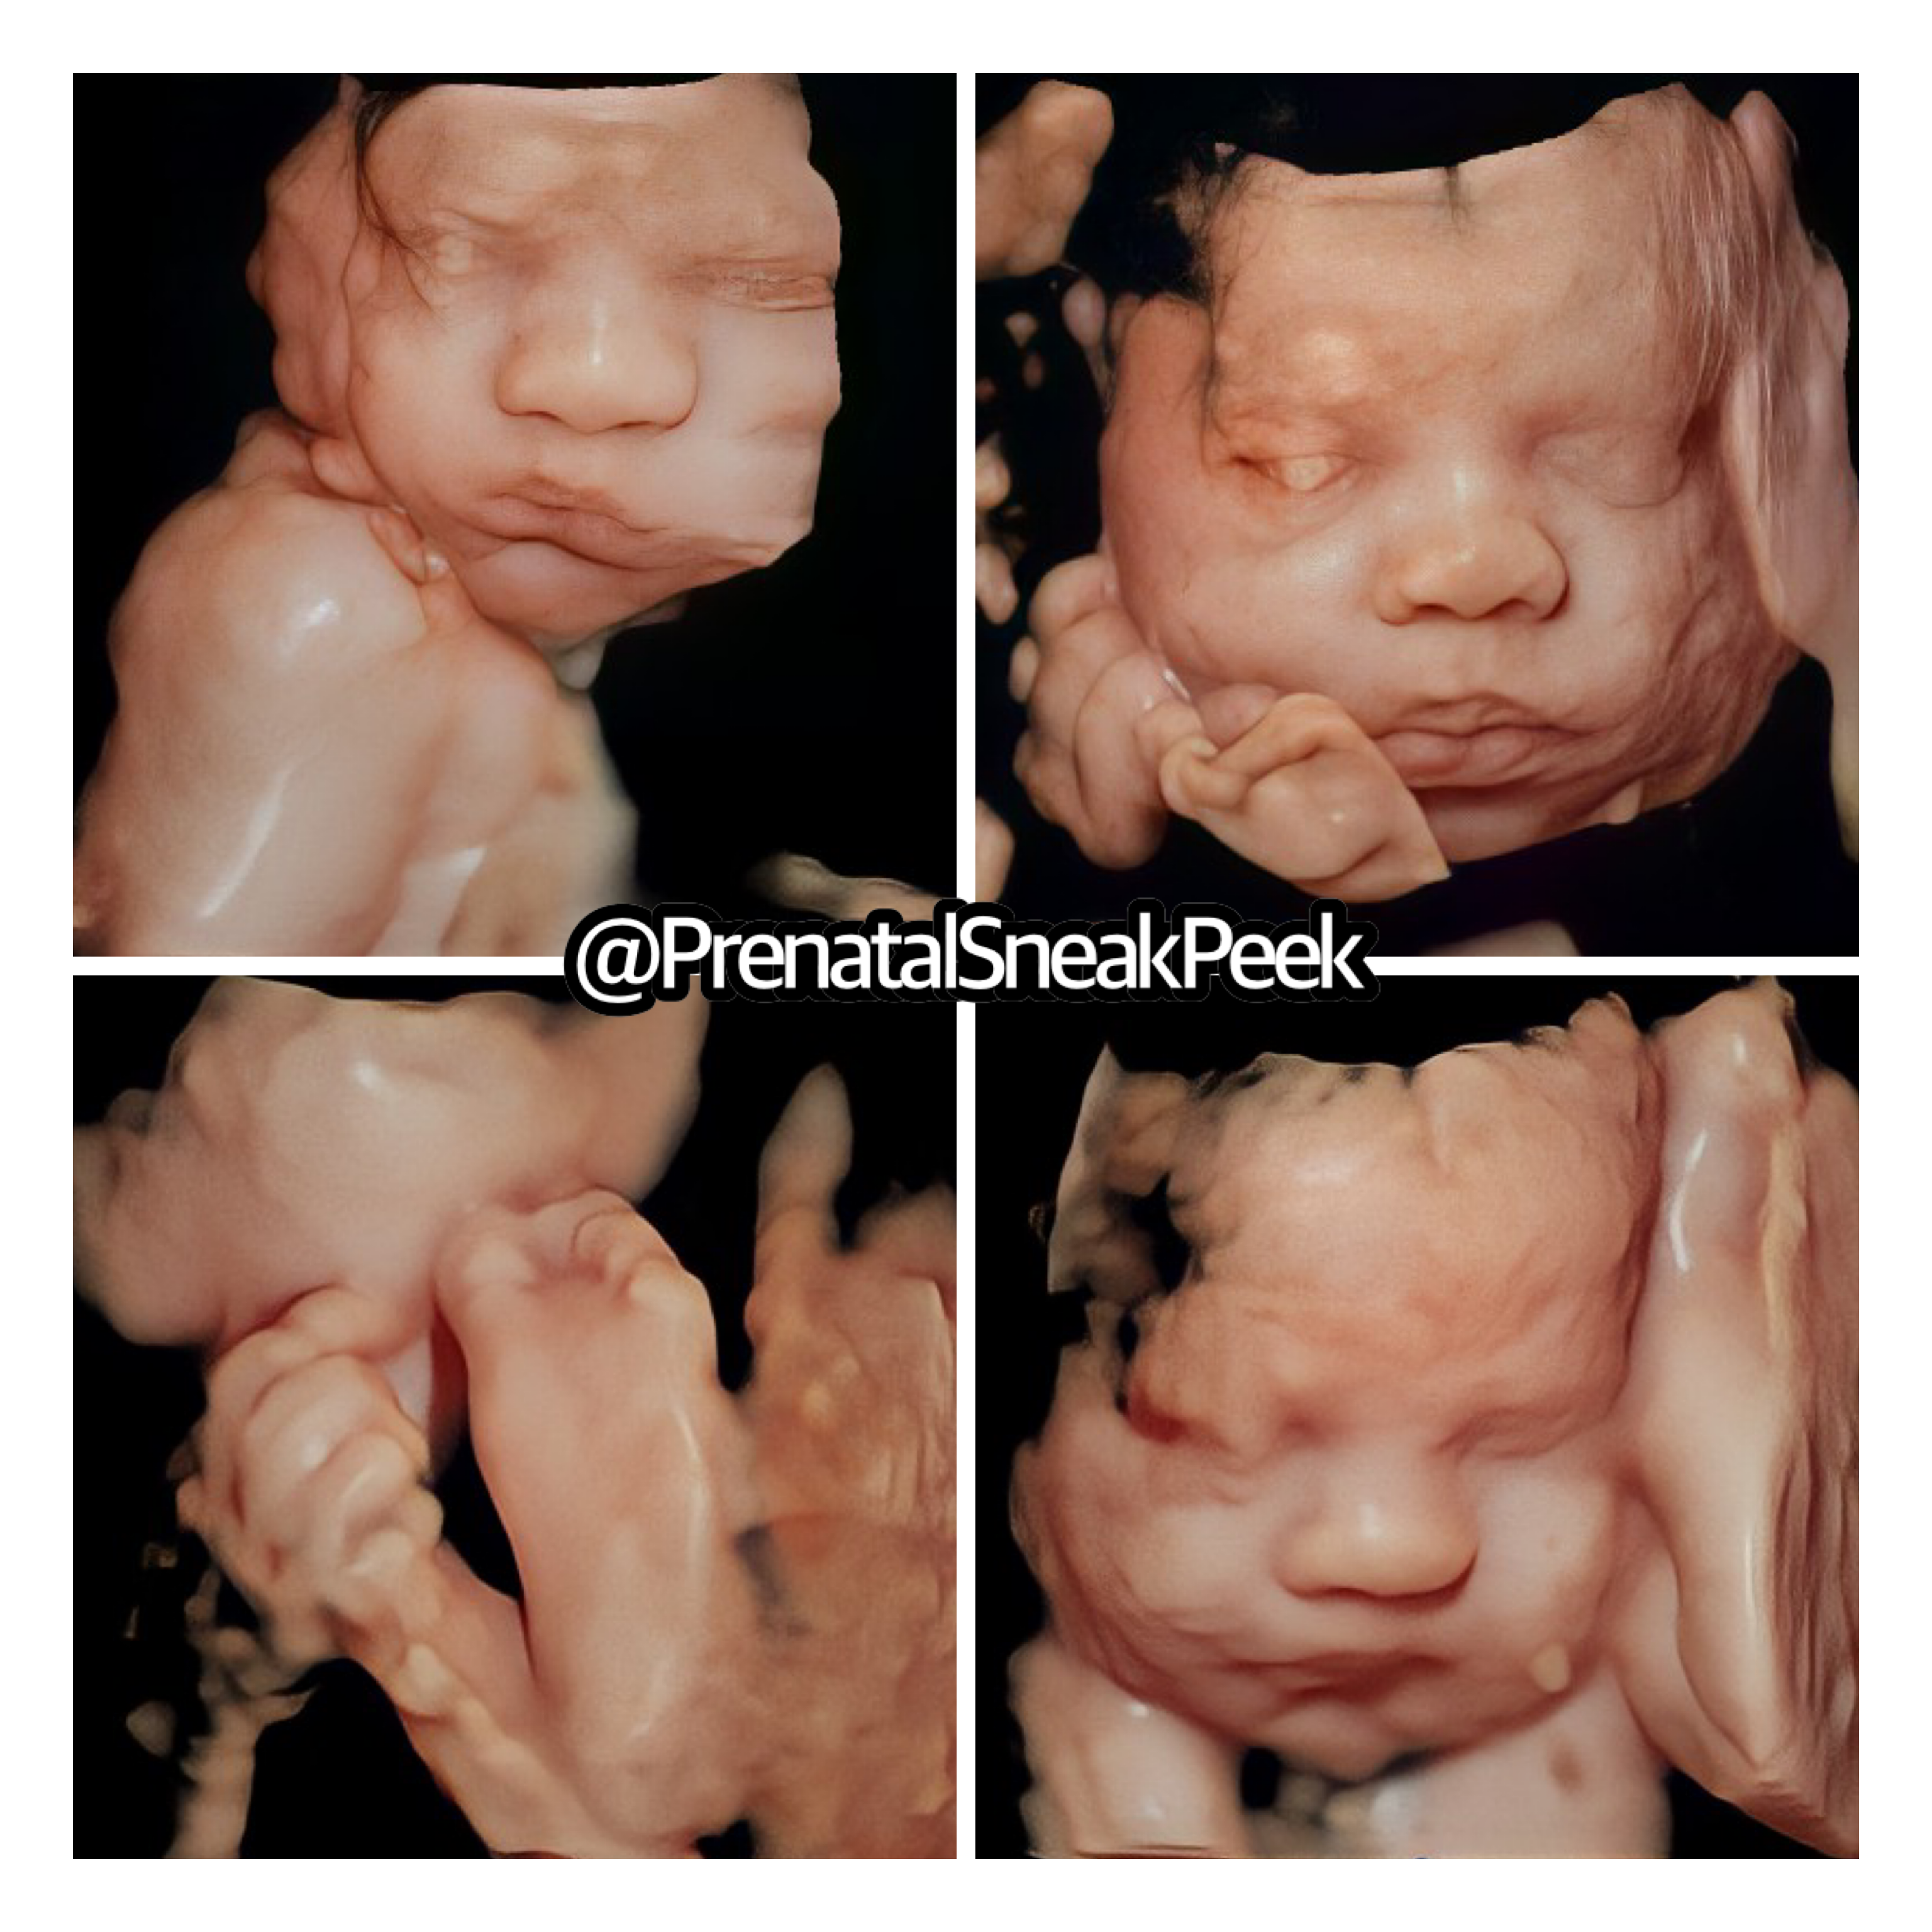

ABOUT PRENATAL SNEAK PEEK

Prenatal Sneak Peek is an elective mobile ultrasound company that provides ultrasounds in the comfort of your home. It is owned and operated out of Bel Air MD. Owner, Kelly Wargo, RDMS is a Registered Diagnostic Medical Sonographer with a specialty certification in OB. She has over 15 yrs. experience in the field of ultrasound. Kelly is the sole operator of her business; therefore, you will get the same quality every time! She also has a heart for saving babies, providing ultrasound services part-time to Options@328 a nonprofit located in Baltimore City.